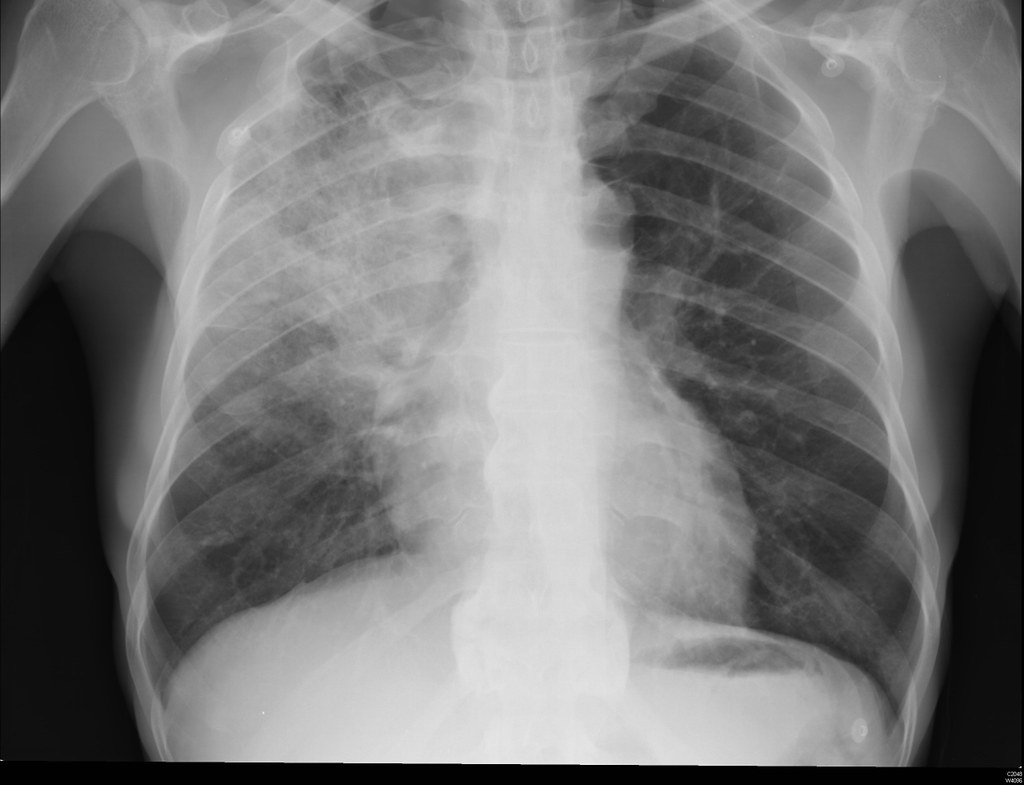

폐렴과 감기 진단

영상 검사에서 감기의 흉부 조각은 대부분 변화가 없는 반면 폐렴은 폐 결이 두꺼워지거나 침윤되는 경우가 많습니다.